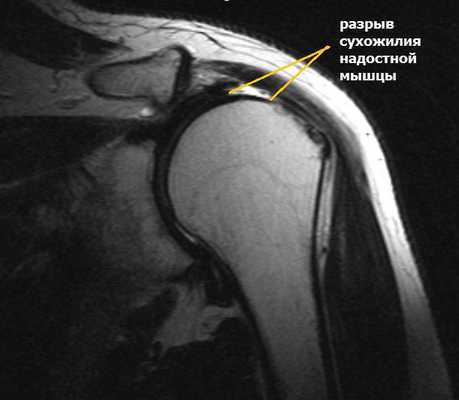

Повреждения вращательной манжеты

К повреждению сухожилий вращательной манжеты могут приводить несколько причин:

Сужение пространства между акромионом и головкой плечевой кости (импинджмент-синдром) возникает на фоне особого строения акромиального отростка или после получения травмы. Сухожилие надостной мышцы, проходящее в данном пространстве, попадает как бы в тиски и постепенно сдавливается.